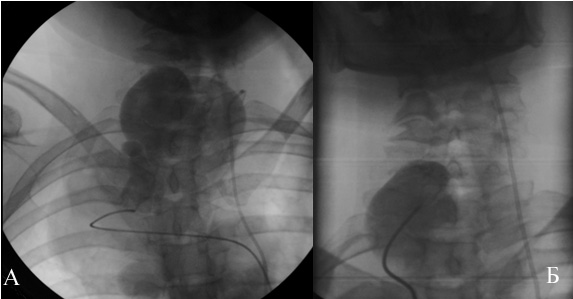

Рис.7 Закрытие аневризмы имплантацией устройства «Amplatzer» для закрытия открытого артериального протока .

А) ангиограмма левой позвоночной артерии до операции (передне-задняя проекция)

Б) ангиограмма полости аневризмы до операции (боковая проекция)

Ангиография брахиоцефальных артерий: восходящая аорта, дуга, нисходящая аорта без патологических изменений. Проксимальный сегмент правой позвоночной артерии извит, расширен. Визуализируется гигантское мешковидное образование размером 85×130 мм от уровня С5, занимающее всю область шеи, подчелюстную область и спускающееся в грудную полость по ходу верхней полой вены (рис.5). Отмечается сужение правой подключичной артерии до 80% при выходе из реберно-ключичного пространства. Правая общая сонная артерия — девиация в среднем отделе. Выполнена ангиография брахиоцефальных сосудов и селективная ангиография полости аневризмы. Верхняя граница аневризмы визуализируется до интракраниального отдела правой позвоночной артерии. При ангиографии левой позвоночной артерии выявлен переток в систему правой позвоночной артерии с контрастированием аневризмы (рис.6). Левые позвоночная, общая сонная артерия — без особенностей. Клинический диагноз: Гигантская аневризма правой позвоночной артерии. Миелопатия от длительного сдавления в шейном отделе позвоночника смешанного генеза (компрессионная, ишемическая). Дисциркуляторная энцефалопатия в вертебро-базилярном бассейне. Нейрофиброматоз I типа (синдром Реклингаузена). Медикаментозное лечение: детралекс, дексазон, эуфиллин, карнитин, мексидол. Учитывая, что полость аневризмы заполнялась как антеградно, так и ретроградно (через базилярную артерию), было решено первым этапом локализовать аневризматический мешок в дистальном отделе эмболизацией позвоночной артерии спиралями GIANTURCO (COOK) доступом через контрлатеральную позвоночную артерию. Однако, в связи с техническими трудностями прохождения проводника и катетера через базилярную артерию, решено воздержаться от выполнения данной процедуры и попытаться закрыть аневризму из антеградного доступа имплантацией устройства «Amplatzer» для закрытия открытого артериального протока в проксимальный отдел правой позвоночной артерии.